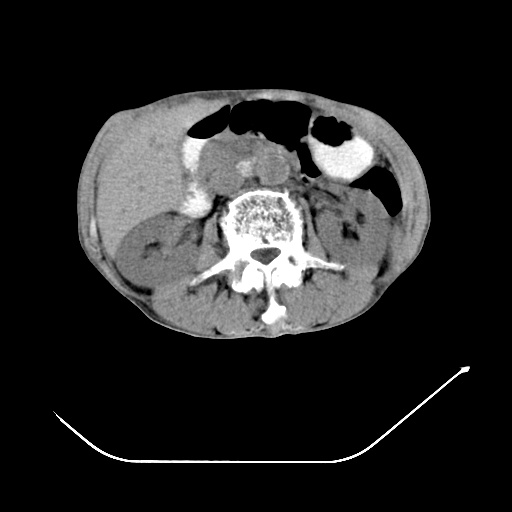

以下是引用zsl6918在2008-8-25 21:55:00的发言:[br]符合右肺周围性肺癌并肺内转移,左肺结核球。双肺肺气肿。腰椎附件转移。

以下是引用随光逐影在2008-8-25 22:03:00的发言:[br]1)考虑右肺下叶周围性肺癌并肺内转移,腰椎附件转移。2)左上肺结核(结核球形成)。3)双肺肺气肿(多发肺大泡形成)。4)双肺门区及纵隔内多发淋巴结钙化。